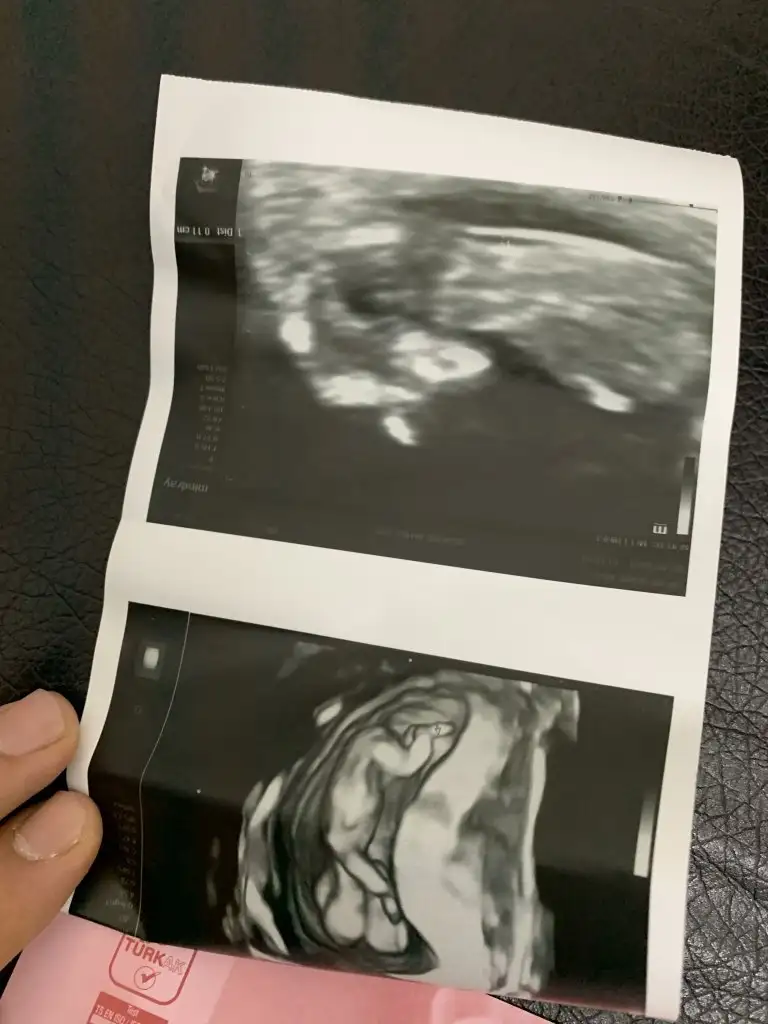

İkra meyra 12 haftalık ken tekrar foto atın demiştiniz burda 12+5 sizce cinsiyet ne ?

Eklentiler

• EDF88188-D37F-4A20-999C-B32BE1D02EF0.webp

EDF88188-D37F-4A20-999C-B32BE1D02EF0.webp

37 KB · Görüntüleme: 56